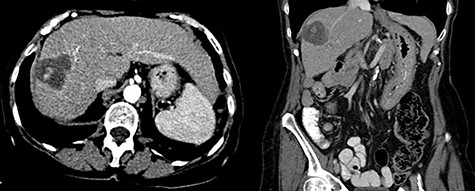

Three months post-radioembolization, ceCT abdomen and pelvis showed that the large right hepatic lobe mass was almost entirely necrotic with central hemorrhage and was decreased in size, measuring 4.2 cm. The right hepatic artery provided minor supply to the Segment IV lesion, and therefore this lesion had also decreased in size from 1.8 to 1 cm (Fig. 5). There were no additional hepatic lesions demonstrated. The AFP level dropped from 119 pre-treatment to 8.4 ng/ml (normal AFP < 8.3 ng/ml).

Three month follow-up ceCT demonstrates necrosis and involution of the lesion as well as spontaneously hyperdense material centrally consistent with hemorrhage.